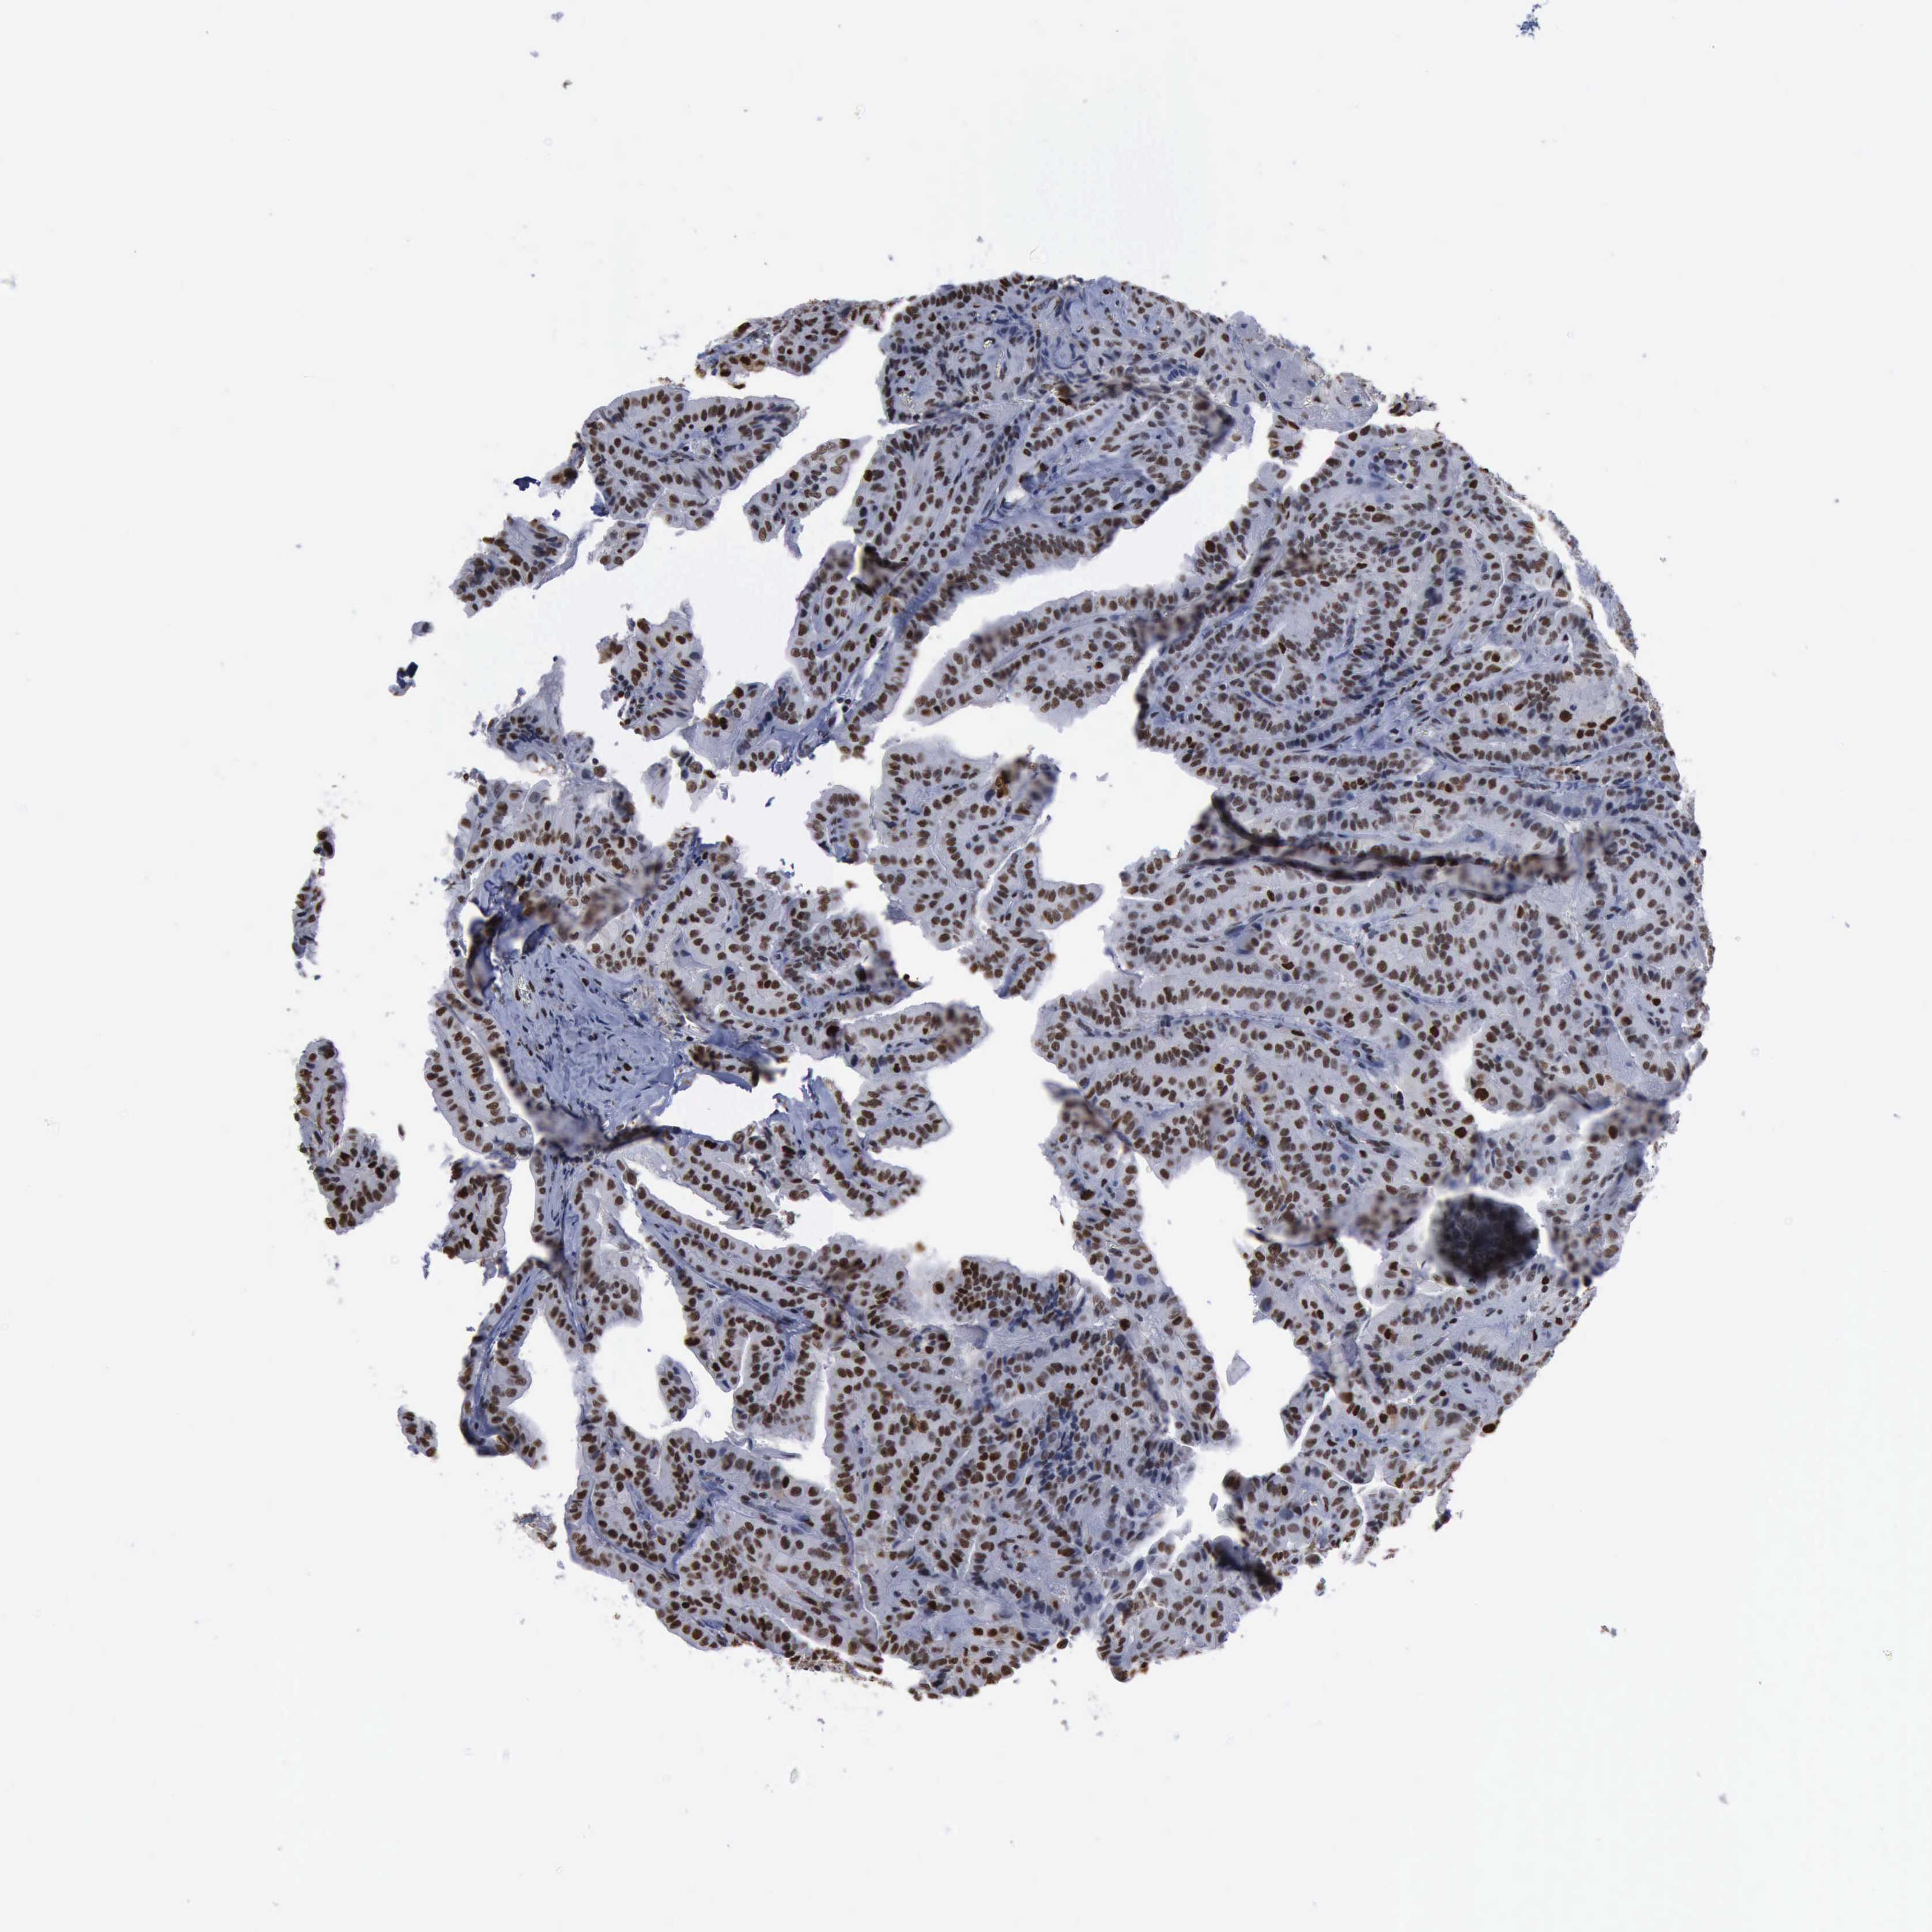

THYROID CANCER - Protein expressioni

A mouse-over function shows sample information and annotation data. Click on an image to view it in a full screen mode. Samples can be filtered based on level of antibody staining by selecting one or several of the following categories: high, medium, low and not detected. The assay and annotation is described here.

Note that samples used for immunohistochemistry by the Human Protein Atlas do not correspond to samples in the TCGA dataset.

Antibody stainingi

Antibody staining in the annotated cell types in the current human tissue is reported as not detected, low, medium, or high, based on conventional immunohistochemistry profiling in selected tissues. This score is based on the combination of the staining intensity and fraction of stained cells.

Each image is clickable and will lead to virtual microscopy that enables deeper exploration of all samples and also displays staining intensity scores, fraction scores and subcellular localization as well as patient and tissue information for each sample.

Staining

High

Medium

Low

Not detected

Intensity

Strong

Moderate

Weak

Negative

Quantity

>75%

75%-25%

<25%

None

Location

Nuclear

Cytoplasmic/membranous

Cytoplasmic/membranous,nuclear

Papillary adenocarcinoma, NOS

Follicular adenoma carcinoma, NOS

Carcinoma, NOS